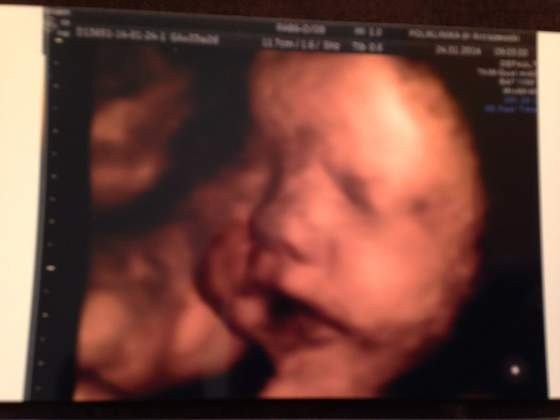

Bylam na wizycie i maly wazy 2130 g wszystko wyglada ok ladnie przybiera

wrzucam wam zdjecia

Załączniki

Tigi ja z polowkowego to tez mam kiepskie bo po pierwsze ze maly ciagle sie zaslanial a po drugie usg robil mi nie moj lekarz bomyaka maja zasde ze polowkowe robi inny specjalista i jemu nie chcialo sie troche pokombinowac zeby maly sie ladnie ustwail a dzisiaj zaszlam do swojego gina i mowie panie doktorze poprosze ladne zdjecia do albumu rodzinnego bo juz dawno nie mialam ladnych zdjec i sie chlopina postaral :-)